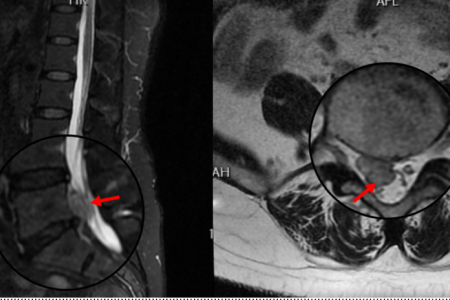

患者阳某某,女,50岁,因反复腰部疼痛7年加重,并右下肢疼痛麻木半月到衡南县人民医院就诊。骨科二区主任陈轼接诊了患者,门诊MRI检查发现阳女士为典型L5/S1巨大椎间盘脱出并压迫神经根,保守治疗无效,建议手术治疗。苗惊雷教授与县医院骨科二区专家团队为阳女士量身定制了无需内固定、创伤更小的UBE微创手术方案。术中通过两个7mm的切口,精准摘除脱出髓核,彻底解除神经压迫。术后次日,阳女士下肢症状显著缓解,已可自主下床活动。